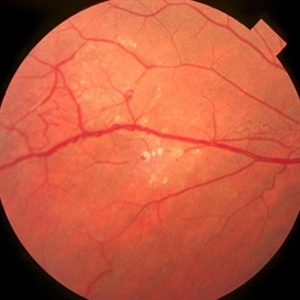

Gyrate Atrophy

Oct 9 2012 by Alan D. Letson, MD

Focal atrophic choroidal lersions in a 12-year-old boy with markedly elevated serum ornithine levels.

Photographer: Beverly Radcliffe

Condition/keywords: gyrate atrophy, ornithine